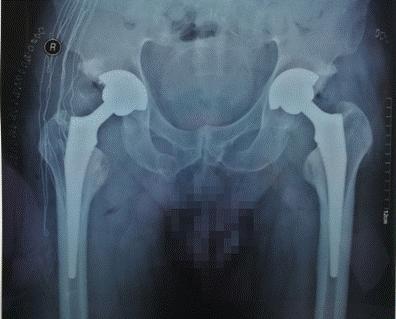

骨外科关节与运动医疗一病区顺利完成了此项手术,术后髋关节假体位置、肢体长度良好,未出现闭孔血管、神经损伤、深静脉血栓等并发症,患者站立感觉良好,康复出院,预计术后三个月可以恢复正常人的步态和生活。

双侧髋关节手术后影像